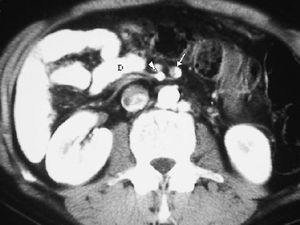

La forma más frecuente es la ausencia de rotación intestinal, que implica importantes alteraciones anatómicas valorables tanto en la ecografía como por la TC. Los principales hallazgos radiológicos son: alteración en la posición del duodeno, que no pasa entre la aorta y la arteria mesentérica superior (AMS); la localización en el hemiabdomen derecho de las asas de intestino delgado y en hemiabdomen izquierdo las de intestino grueso, y una verticalización o inversión de los vasos mesentéricos respecto a su posición normal, quedando la AMS a la derecha y la vena mesentérica superior (VMS) a la izquierda1,2 (fig. 1).

Fig. 1--Malrotación intestinal. (A) y (B) Tomografía computarizada con contraste oral e intevenoso mostrando inversión de la arteria mesentérica superior (AMS) (punta de flecha) y la vena mesentérica superior (flecha). La tercera porción duodenal (D) no cruza la línea media entre la aorta y la AMS, localizándose las asas de yeyuno a la derecha.